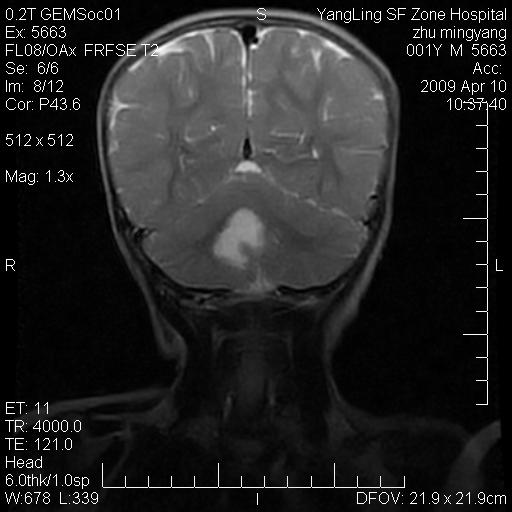

患者:1岁半,两天前外伤收住我院,ct检查小脑占位

考虑星形细胞瘤,建议增强

髓母细胞瘤或血管母细胞瘤,增强后可以鉴别;影像资料见 <。鱼博浪老师的《中枢神经系统ct与mr鉴别诊断》 小脑部肿瘤章节。

髓母细胞瘤或血管母细胞瘤!支持!

支持考虑髓母细胞瘤

考虑----髓母细胞瘤可能性大

考虑髓母细胞瘤或室管膜瘤。

支持髓母细胞瘤。

考虑髓母细胞瘤。

考虑髓母细胞瘤或星形细胞瘤

考虑髓母细胞瘤.

考虑髓母细胞瘤可能性大。

小脑肿瘤.考虑髓母细胞瘤可能.

就病灶部位及临床资料首先考虑髓母.